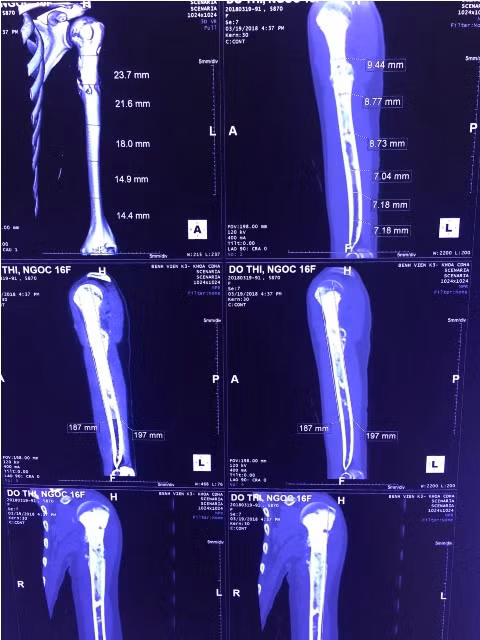

Phim chụp cánh tay sẽ phẫu thuật của bệnh nhân N.

ThS. Nguyễn Trần Quang Sáng (Khoa Ngoại bụng 2, bệnh viện K) cho biết: “Trước đây thường phẫu thuật cắt cụt cánh tay hoặc cắt đầu trên xương cánh tay của bệnh nhân, sau đó treo phần còn lại vào ổ chảo. Bởi vậy toàn bộ cánh tay sẽ mất chức năng, thậm chí sau một thời gian cánh tay có thể sẽ sệ xuống, làm bệnh nhân khó chịu quay lại xin cắt cụt. Với trường hợp bệnh nhân N. ekip phẫu thuật đã cắt đầu trên xương cánh tay cách khối u trên 2cm để tránh tái phát sớm, dự kiến đoạn xương cắt dài 18cm.

Tuy nhiên ở Việt Nam hiện tại khớp vai nhân tạo chuôi dài nhất là 13 cm. Do vậy vấn đề khó khăn đặt ra là khi thay khớp vai nhân tạo sẽ làm ngắn chi ảnh hưởng chức năng của khớp. Kíp phẫu thuật đã tiến hành ghép thêm đoạn xương đồng loại sau đó mới đưa chỏm nhân tạo vào khớp vai, giúp phục hồi chức năng chi, khớp cũng như thẩm mỹ cho bệnh nhân”.